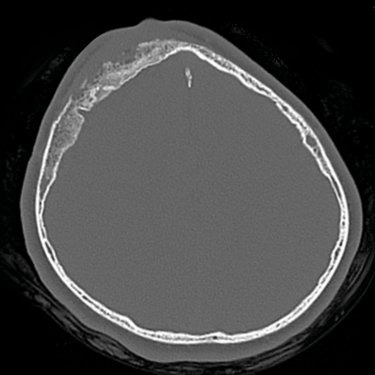

Osteomielitis Frontal | Diagnóstico por Tomografía

La osteomielitis frontal es una infección del hueso craneal que generalmente se origina como complicación de una sinusitis frontal no tratada o mal resuelta. Clínicamente puede manifestarse con dolor localizado, fiebre, edema frontal y signos inflamatorios en la región afectada. El método diagnóstico de elección es la tomografía computarizada (TC), que permite identificar destrucción ósea, engrosamiento cortical e incluso colecciones asociadas. Este estudio es esencial para diferenciarla de otras lesiones y planificar un tratamiento adecuado, que puede incluir antibióticos de amplio espectro y cirugía para drenar y desbridar el tejido infectado, evitando complicaciones intracraneales graves.